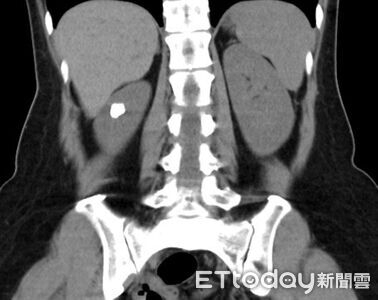

罕見腎結石害反覆泌尿道感染 醫曝拖延後果:腎化膿+敗血症

一名50歲女性反覆泌尿道感染,原以為只是一般感染問題,就醫檢查才發現竟和天生的「腎盞憩室」與結石有關,經微創輸尿管鏡碎石手術取出結石並擴大通道,長期的感染困擾終獲緩解。